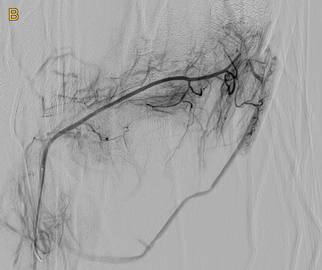

Nach sorgfältiger lokaler Betäubung wird minimalinvasiv über ein Gefäß in der Leiste ein weniger als zwei Millimeter dünner Katheter bis in die winzigen Seitenäste der Gelenkarterien vorgeschoben. Mittels Einschwemmung kleiner Kügelchen („Mikrosphären“) können diese Seitenäste anschließend teilweise verschlossen („embolisiert“) werden. Die Blutversorgung des Gelenkes insgesamt wird hiervon nicht beeinflusst. Lediglich die überschießende Durchblutung wird ganz lokal reduziert.